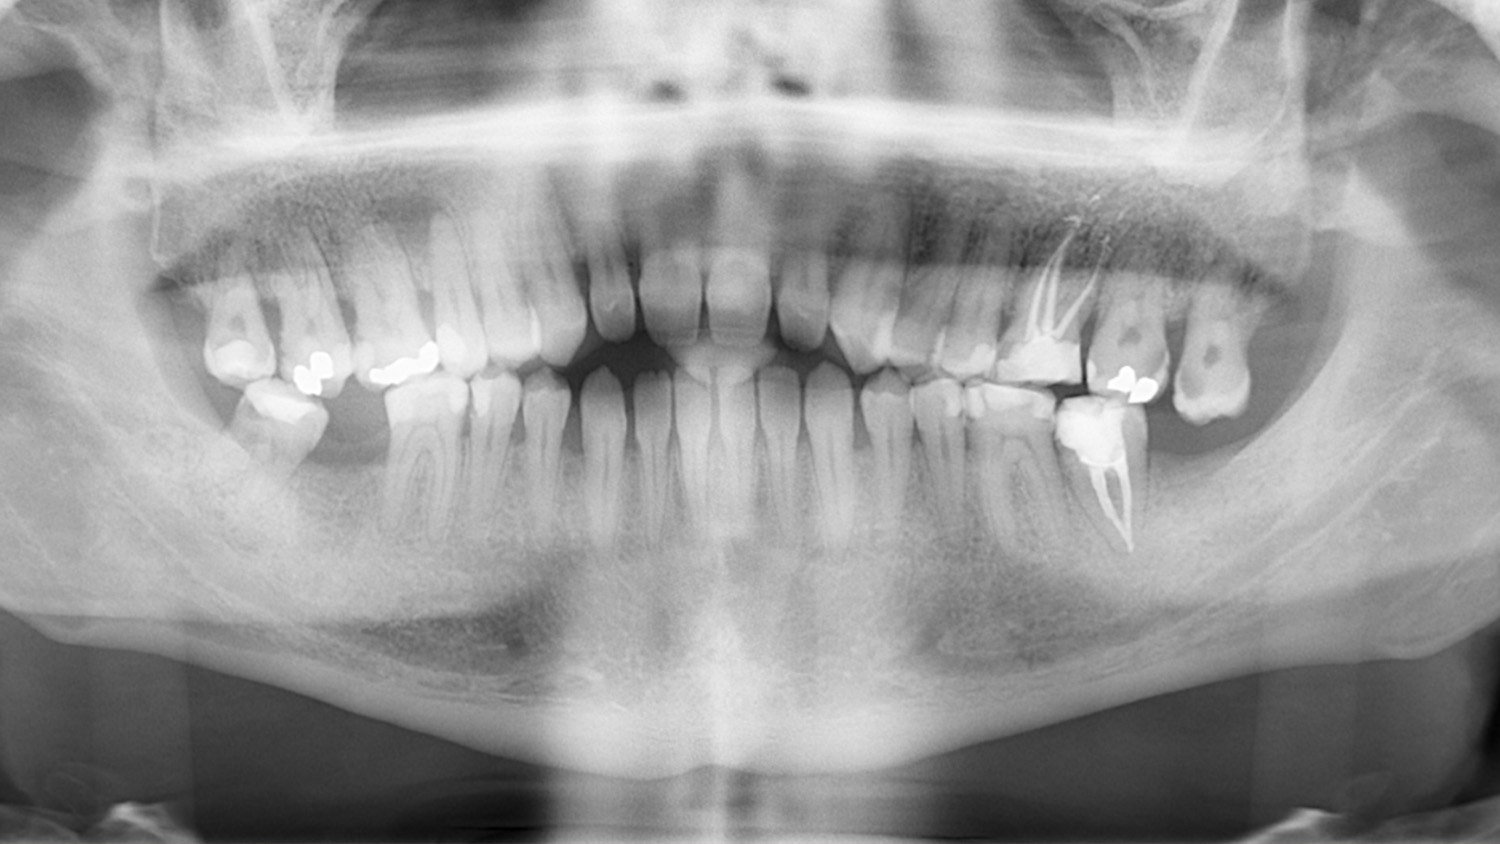

A 27-year-old male patient presented to the orthodontic practice after being referred by his general dentist. His primary concern was improving masticatory function. The patient had no notable medical history, nor had he received prior orthodontic treatment.

Extraoral analysis revealed a facial biotype consistent with a Class III malocclusion, maxillary compression, a gingival smile, mandibular asymmetry with deviation, and a dolichofacial pattern.

Intraoral examination showed an Angle Class III relationship on both sides, along with an anterior open bite. Additionally, a narrow maxilla with a bilateral posterior crossbite was observed.

The patient was informed of various treatment options, including combined orthognathic surgery and orthodontic appliances. However, he opted against surgery. Consequently, a compensatory orthodontic treatment plan using MARPE (Mini-Implant Assisted Rapid Palatal Expander) and Spark Aligners was chosen, after the extraction of the existing third molars and treatment of the cavities.

The primary goal of the treatment was to correct the transverse deficiency of the maxillary arch (>5 mm) and resolve the skeletal crossbite. MARPE was used to address this transverse issue.